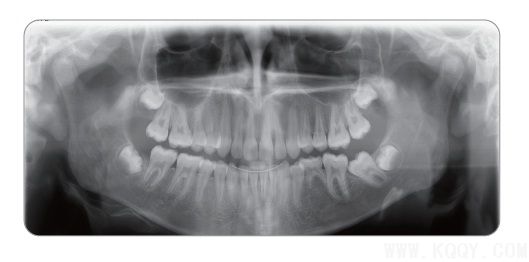

成人全景圖:顯示上下牙列、牙槽骨、神經(jīng)管及TMU,圖像均勻,前牙區(qū)結(jié)構(gòu)也可清晰顯示

前牙掃描層增厚技術(shù)與傳統(tǒng)的前牙掃描攝影技術(shù)相比,提高了病人前牙區(qū)圖像質(zhì)量

CRANEX D將前牙掃描層厚增加50%,提高前牙區(qū)圖像質(zhì)量,并使病人定位簡便。